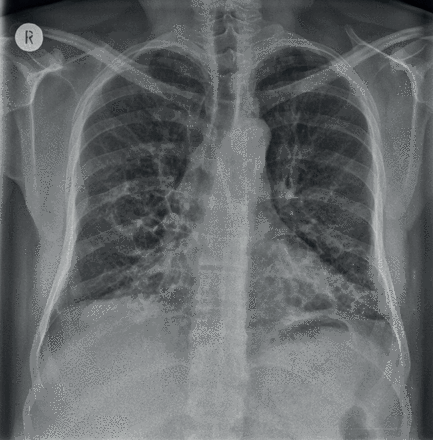

影像学检查显示双肺下叶广泛存在多个囊状透亮区,伴有气道壁增厚及扩张表现。尽管囊性纤维化晚期也可出现显著支气管扩张,但其病变分布通常更为弥散,且以上肺野为主。特发性肺纤维化的胸部 X 光片异常表现则多位于肺外周及基底部位。本病例中,肋膈角未受累及。

该患者确诊为囊性支气管扩张,其发病可追溯至童年时期经历的一次严重感染,此次感染直接诱发了支气管扩张的形成。